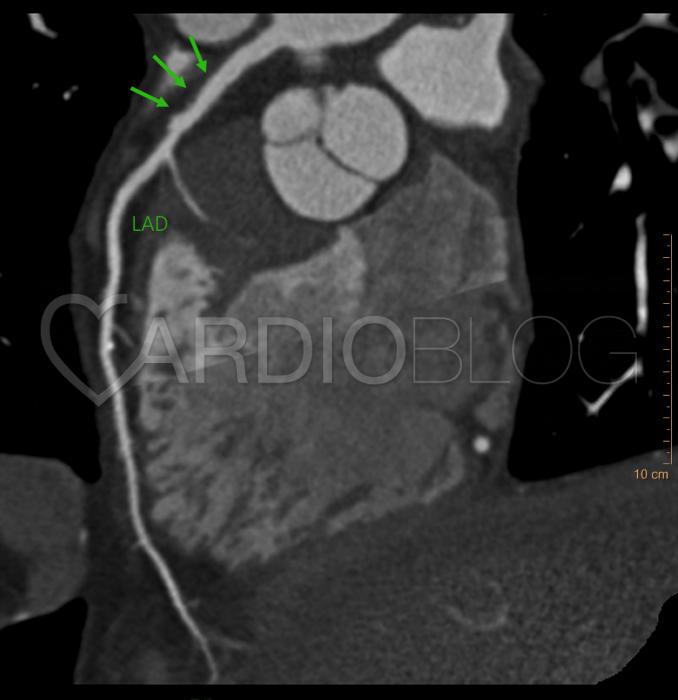

<p>Egy 24 éves Marfan-szindrómás nőbeteg esetét ismertetjük, akinél profilaktikus Bentall-műtét történt nagyfokú aorta aneurizma és III. fokú aortabillentyű elégtelenség miatt. A műtéti beavatkozás lényege, hogy a kitágult aortagyököt egy műérrel helyettesítik, és a proximális szakaszán egy kétlemezes mű-aortabillentyű is behelyezésre kerül. A koszorúerek szájadékát ehhez az úgynevezett „conduit”-hoz varrják hozzá. A betegnél a műtét után 6 héttel terhelésre ventrikuláris tachikardiát észleltünk, majd kamrafibrilláció miatt CPR-t hajtottak végre, továbbá ezt követően ICD beültetés történt. A Bentall-műtét során re-implantált koszorúerek szájadékának megítélése céljából koronária CT vizsgálatra jegyeztük elő (1. kép).</p>

<p style="text-align: center;"><strong><a href="http://www.cardioblog.hu/wp-content/uploads/Marfan1.jpg" target="_blank"><img class="aligncenter size-large wp-image-2655" title="Marfan1" src="http://www.cardioblog.hu/wp-content/uploads/Marfan1-704x442.jpg" alt="" width="700" height="439" /></a></strong></p>

<p><strong><em>1. Kép:</em></strong><em> A Bentall-műtetet követően 6 héttel a koronária CT vizsgálat a koszorúér szájadékokban szűkületet nem igazolt, a felvétel megfelelt a posztoperatív állapotnak, a graft megfelelően helyezkedett el. A sárga nyilak a koszorúereket, míg a zöld nyilak a koszorúerek szájadékait jelölik. </em></p>